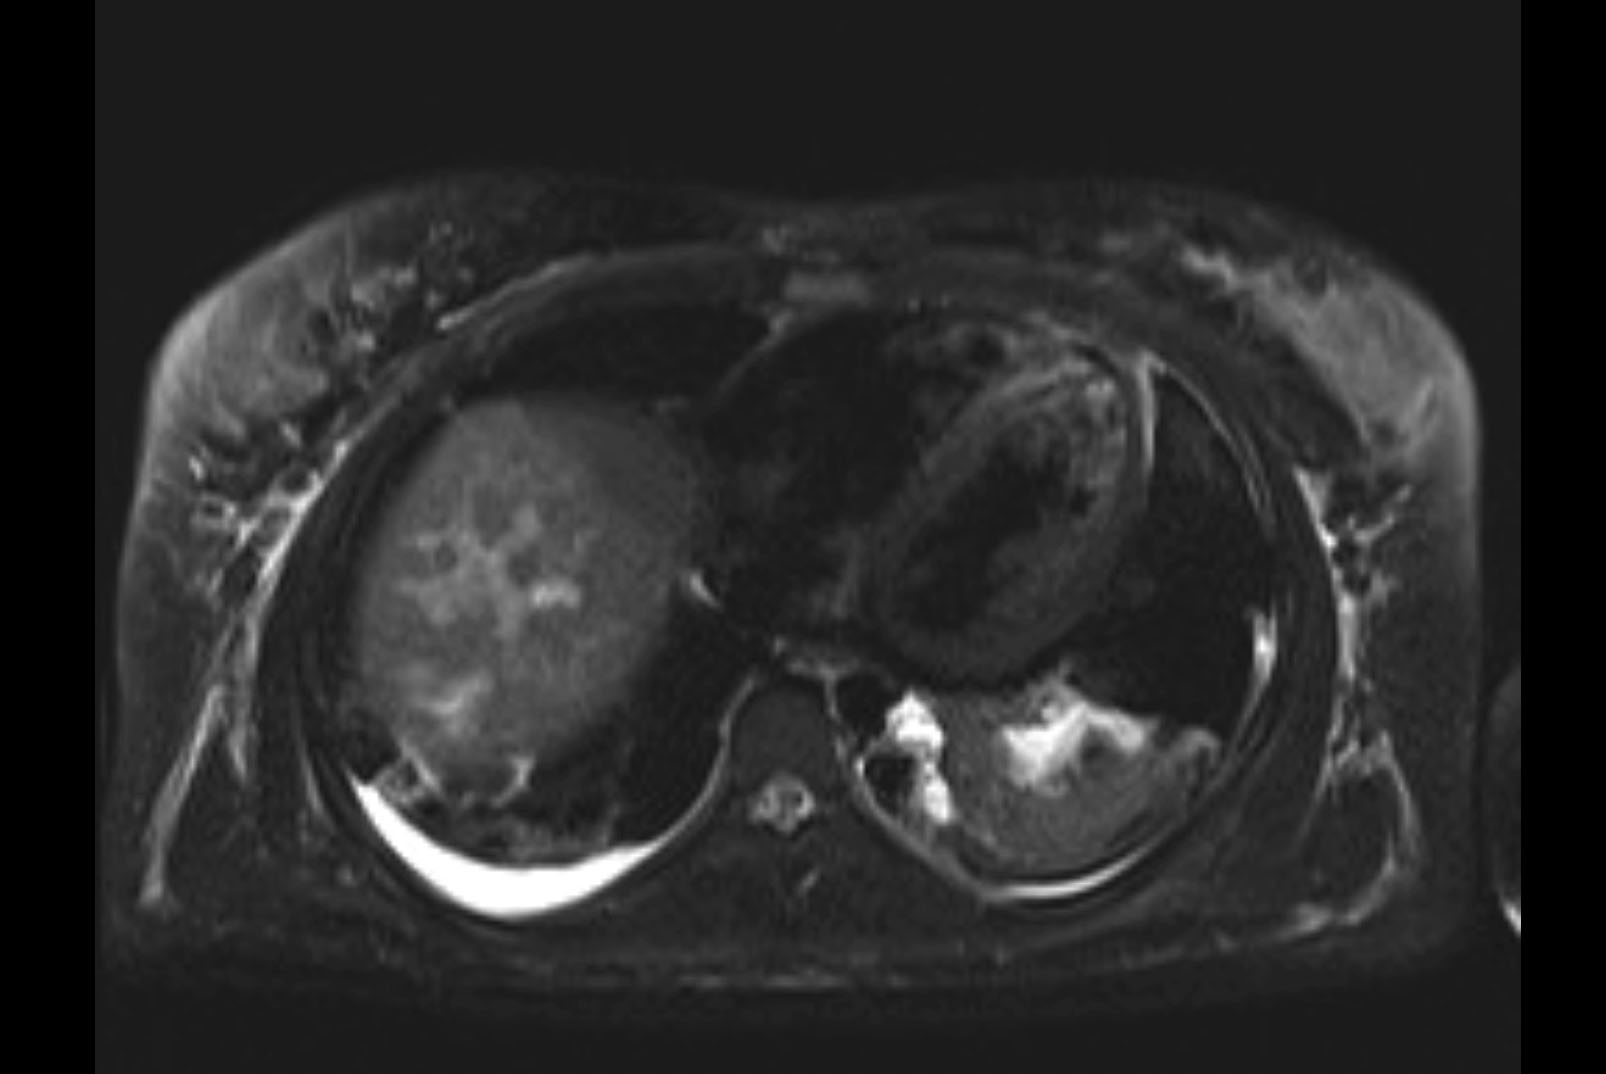

Imaging Analysis

Look through the patient's CT scan to identify any areas of concern for the necessary procedure.

MRI T2

Based on initial findings, which issue(s) would you be most concerned about?